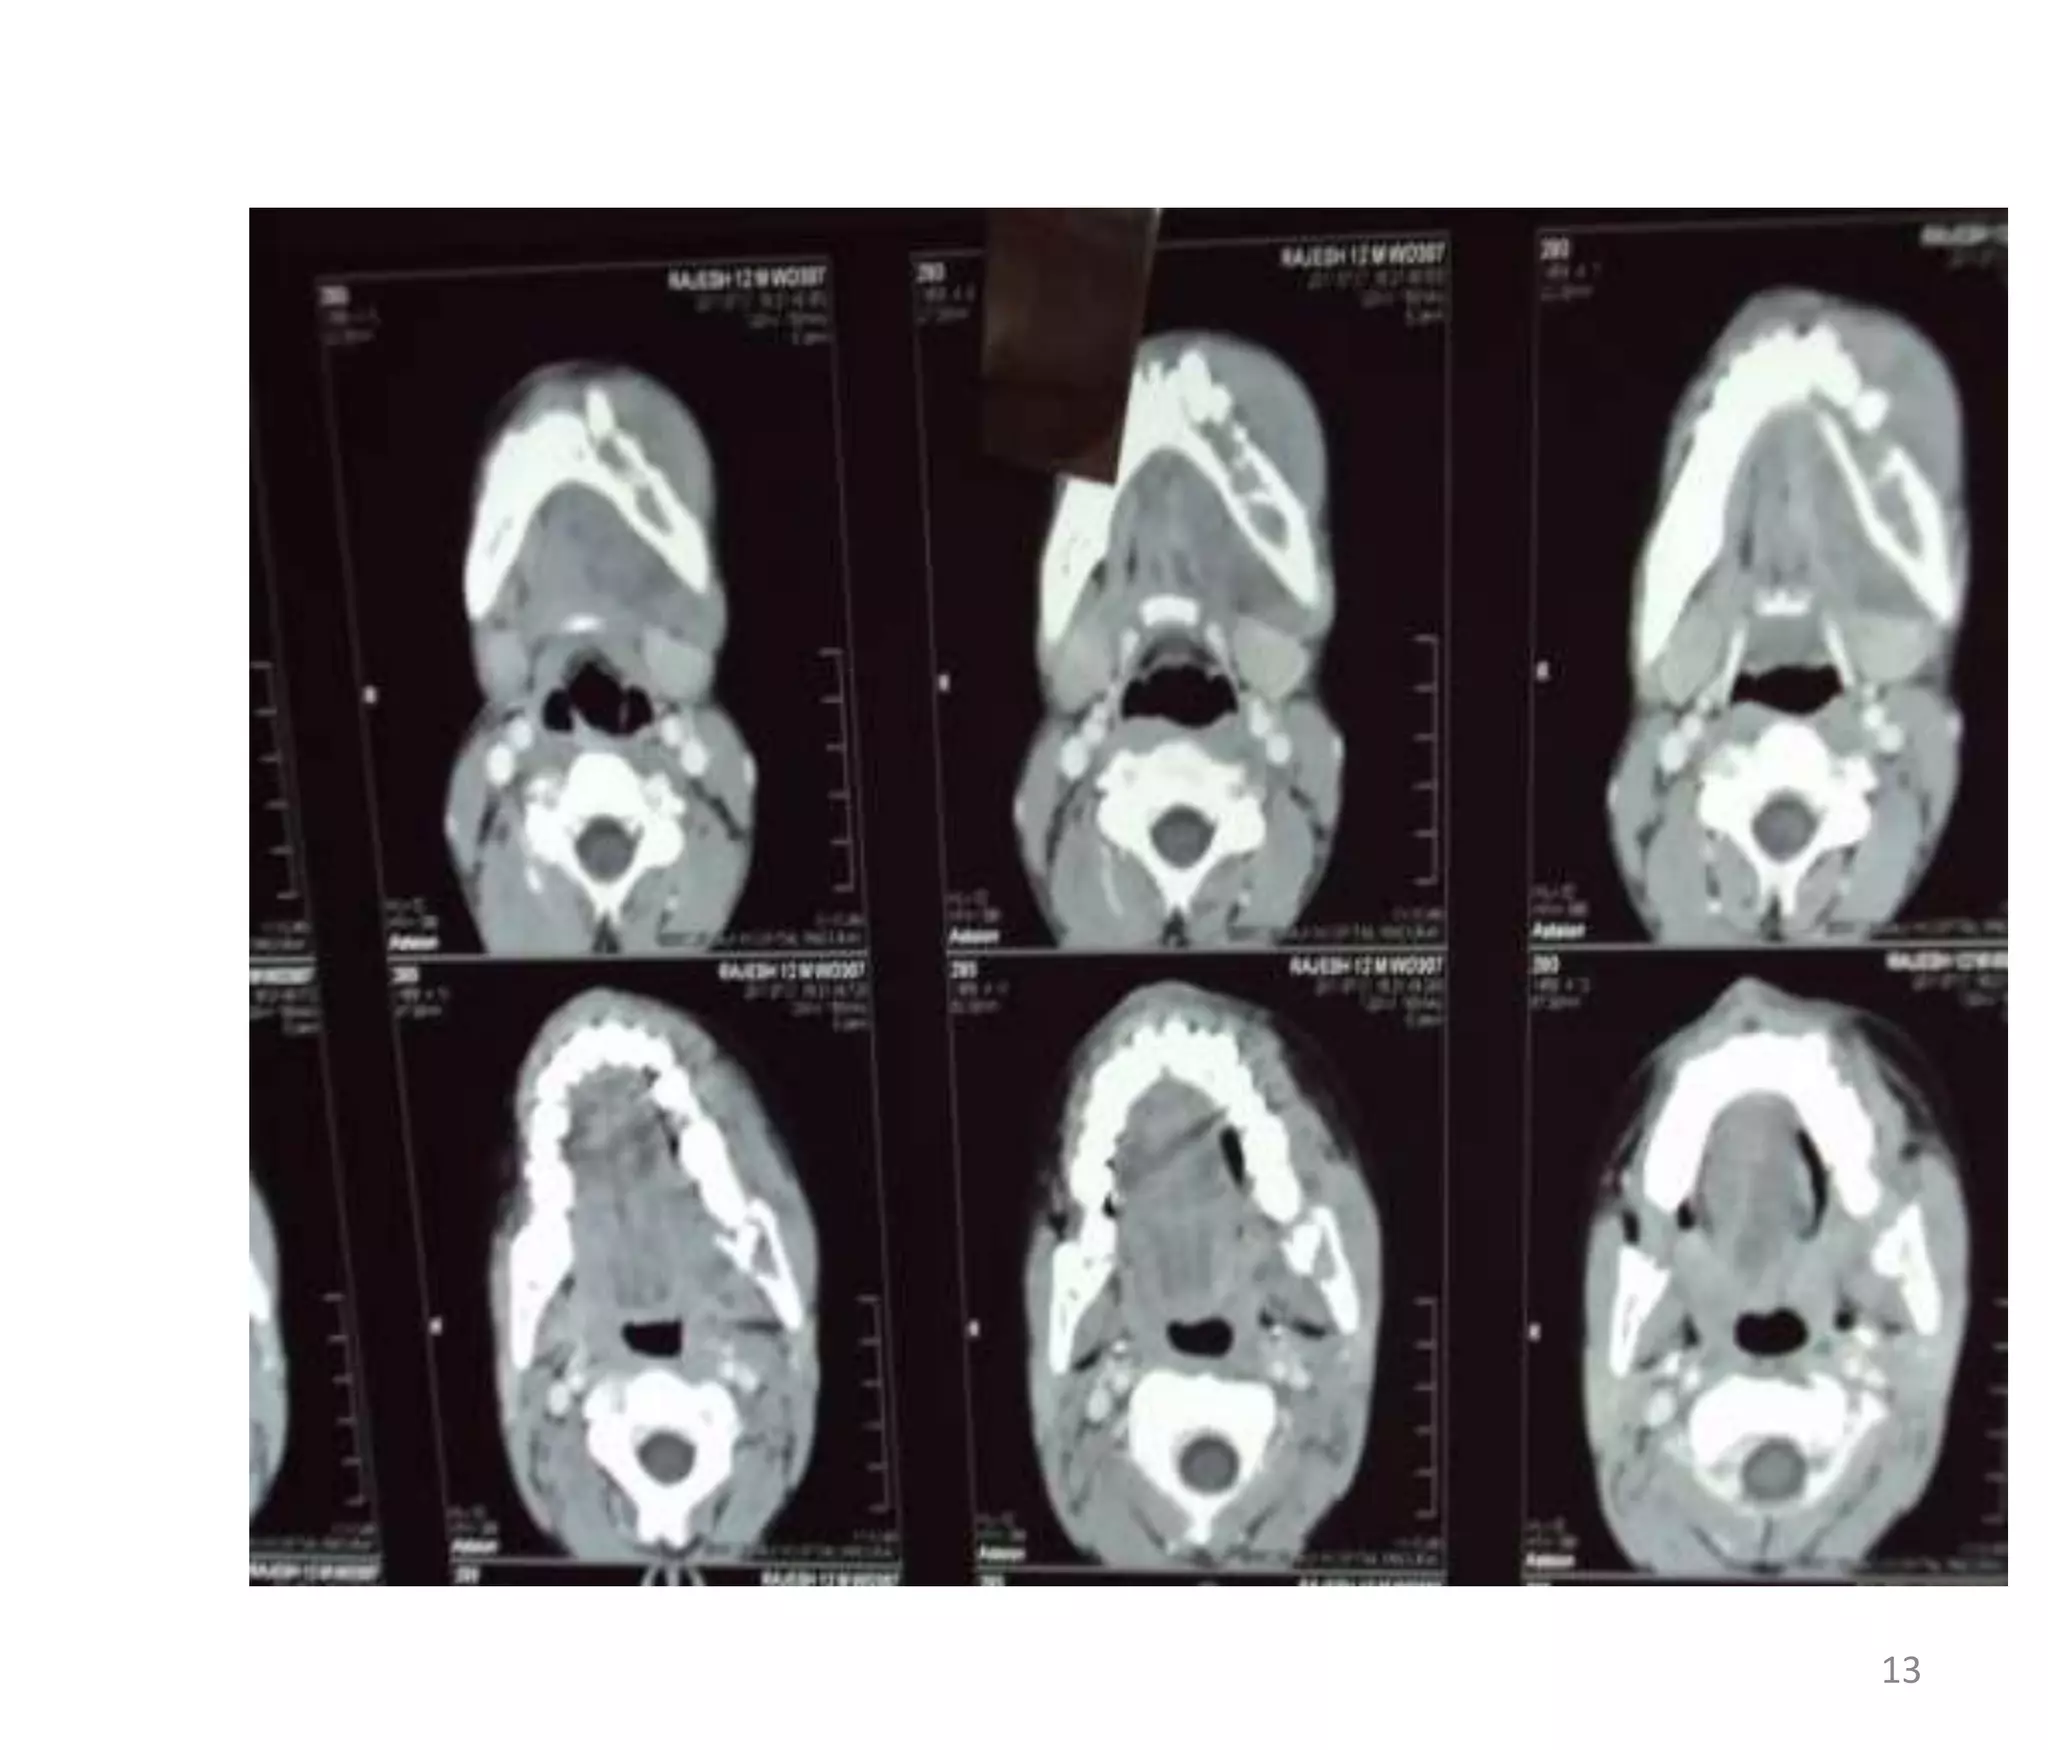

CT - PLAIN

• E/O lytic destruction involving outer horizontal

ramus,angle of the mandible wt large soft tissue

component which extend on both alveolar&buccal

aspect.

• No E/O expansion of bone/periosteal

reaction/calcification.

• E/O destruction of lamina dura &alveolar margin wt

exfoliation of teeth.

CT - CONTRAST

 Moderate heterogenous enchancement.

CT - PLAIN •E/O lytic destruction involving outer horizontal ramus,angle of the mandible wt large soft tissue component which extend on both alveolar&buccal aspect. • No E/O expansion of bone/periosteal reaction/calcification. • E/O destruction of lamina dura &alveolar margin wt exfoliation of teeth. 12

CT - CONTRAST Moderate heterogenous enchancement. 14